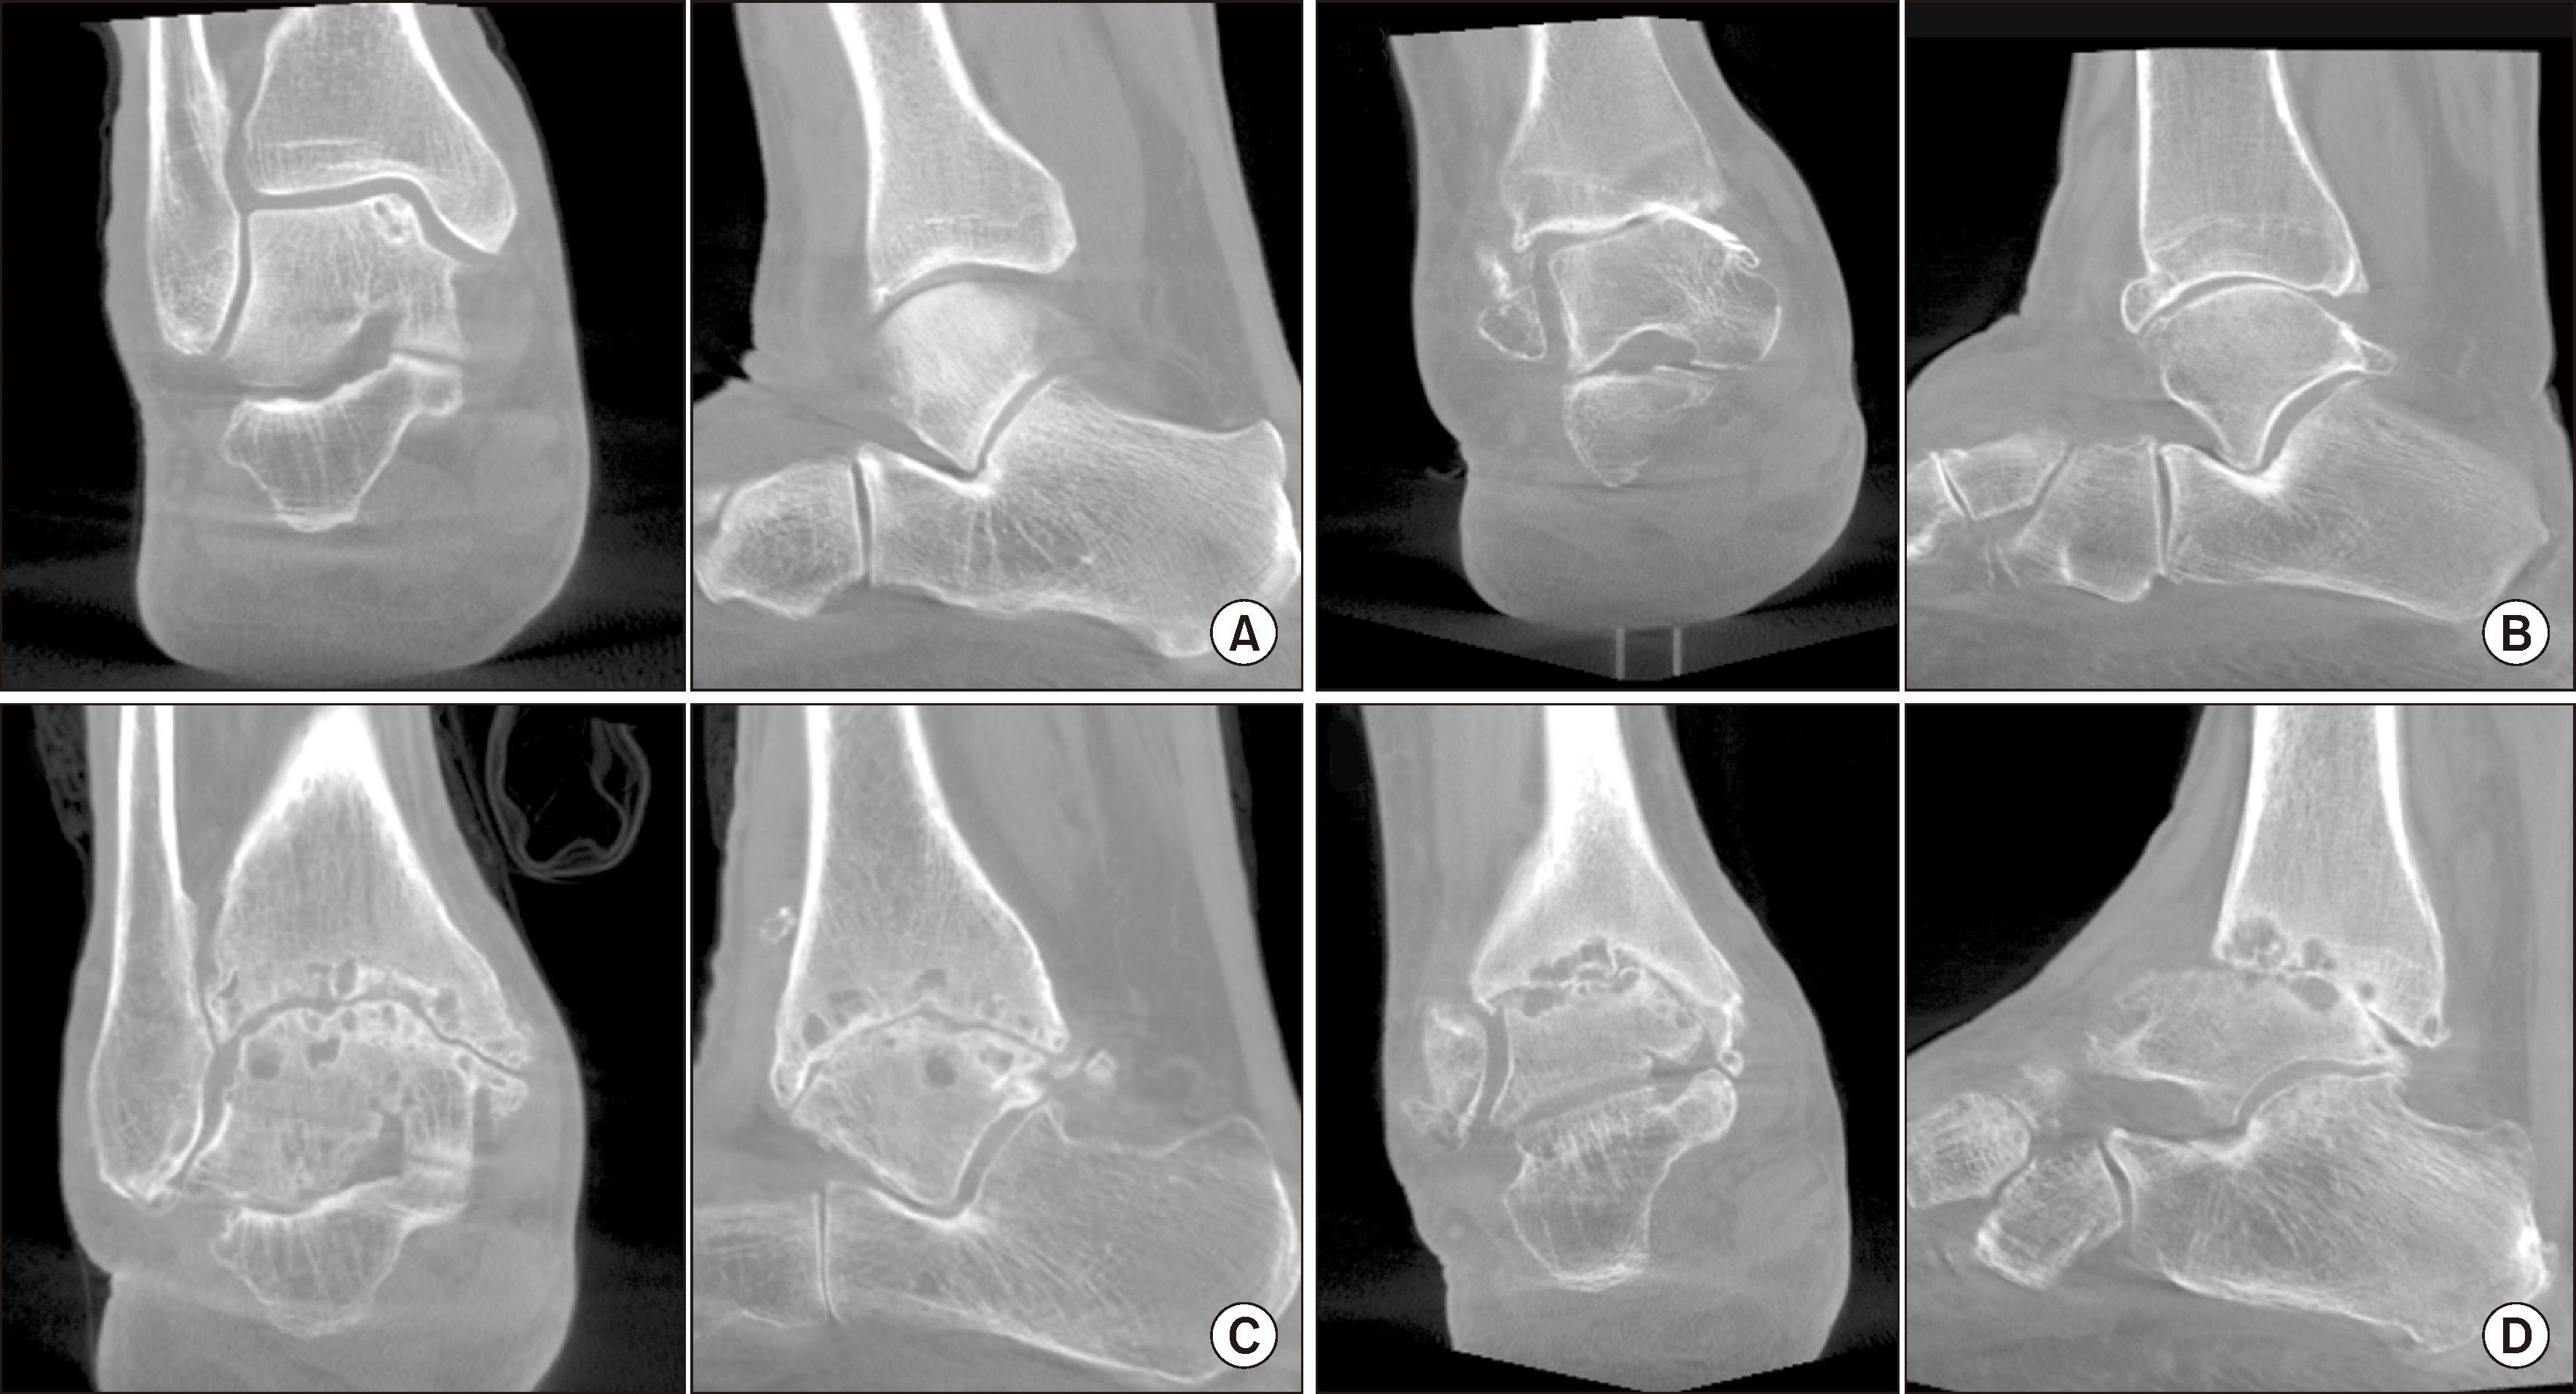

Figure 2

(A) Non-weight-bearing simple radiograph, (B) weight-bearing simple radiograph, (C) Non-weight-bearing computed tomography. (D) Weight-bearing computed tomography. Ankle arthritis diagnosis can vary depending on whether the patient is weight-bearing, not only in simple radiograph but also in computed tomography.

(A) Standing ankle radiograph, (B) anterior, (C) middle, (D) posterior ankle images in coronal plane of weight-bearing computed tomography.

Figure 4

Ankle arthritis classification system by weight-bearing computed tomography. (A) First degree of osteoarthritis with osteophyte formation and joint space narrowing, but not complete loss. (B) Second degree of osteoarthritis with partial or complete loss of joint space. (C) Third degree of osteoarthritis with additional subchondral cysts, with remaining joint surface congruency. (D) Fourth degree of osteoarthritis with aggravated joint surface destruction and incongruence.